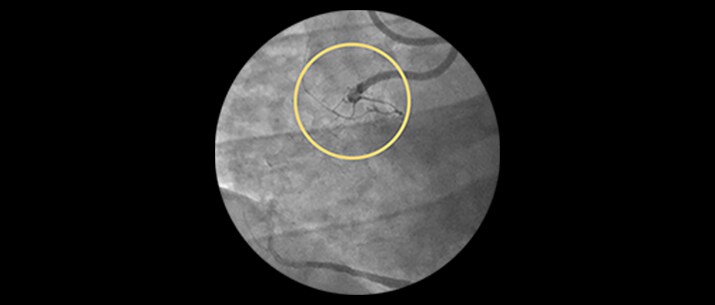

Incidence increases with age, yet older patients are less likely to have PCI attempted.1 Furthermore, 18% of PCIs have a CTO, but less than 5% are being treated.2

ELCA Success and safety rates

| Study | Lesion type | Technical success | Procedural success | MACE Rates* |

| Bilodeau | Calcified and complex coronary lesions | 92.0% | 93.0% | 8.0% |

| | Calcified, uncrossable, resistant coronary lesions | 95.5% | 95.5% | 8.0% |

| Pratsos | Crossable coronary lesions | 98.1% | 99.0% | 0.0% |